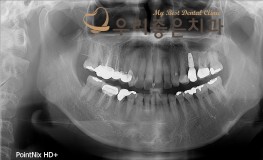

우리좋은치과 임플란트 및 보철치료 (권** 2018.02.24~2018.09.08)

No.203

임플란트

2018-09-15

1293